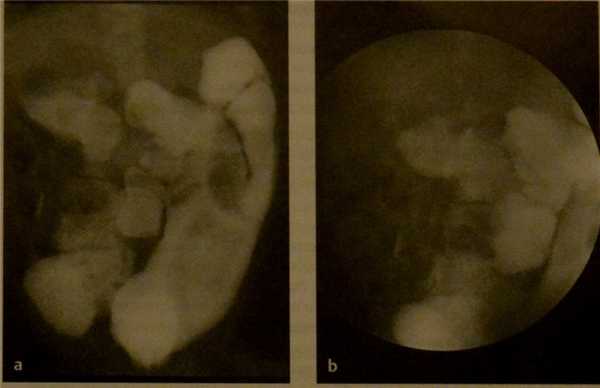

Отсутствие поворота кишки. Снимок верхних отделов желудочно-кишечного тракта. Введение водорастворимого неионного контрастного вещества в двенадцатиперстную кишку через чрескожную эндоскопическую канюлю (одна стрелка). Атипическое расположение двенадцатиперстно-тощего изгиба кишечника (две стрелки) справа от позвоночного столба. Ампула Фатера расположена краниальнее изгиба.

Отсутствие поворота кишечника. Ретроградное контрастирование. Толстая кишка расположена преимущественно в левой половине брюшной полости (а, b). В правой половине брюшной полости визуализируются вздутые петли тонкого кишечника